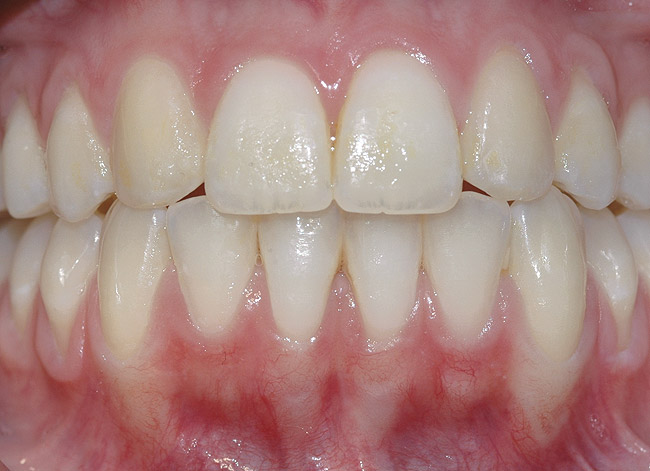

Fig 23. Same patient at 3-year follow-up visit showing a stable esthetic result.

Figure 23

Case Report

A 19-year-old female complaining of gingival recession in the lower right central incisor presented to the authors’ clinic 5 years after completion of orthodontic treatment. The clinical evaluation showed Miller Class II GR accompanied by gingival inflammation (Figure 14). Two years later, despite conservative periodontal treatment, the GR had worsened (Figure 15). The occlusal view shows the presence of a fixed lingual retainer and a significant labial displacement of the root of the affected incisor (Figure 16 and Figure 17). At this stage, orthodontic treatment was considered. The patient was referred for CBCT, which showed no labial bone coverage of the root but 2.5 mm lingual bone thickness at 8 mm distance from the CEJ (Figure 18). After 6 months of orthodontic treatment with fixed appliances (Figure 19), the B-L inclination of the affected tooth was corrected (Figure 20). The frontal clinical view shows narrowing of the GR (Figure 21). Surgical coverage of the exposed root was subsequently performed by connective tissue graft (Figure 22). A long-term stable and esthetic result was achieved (Figure 23).